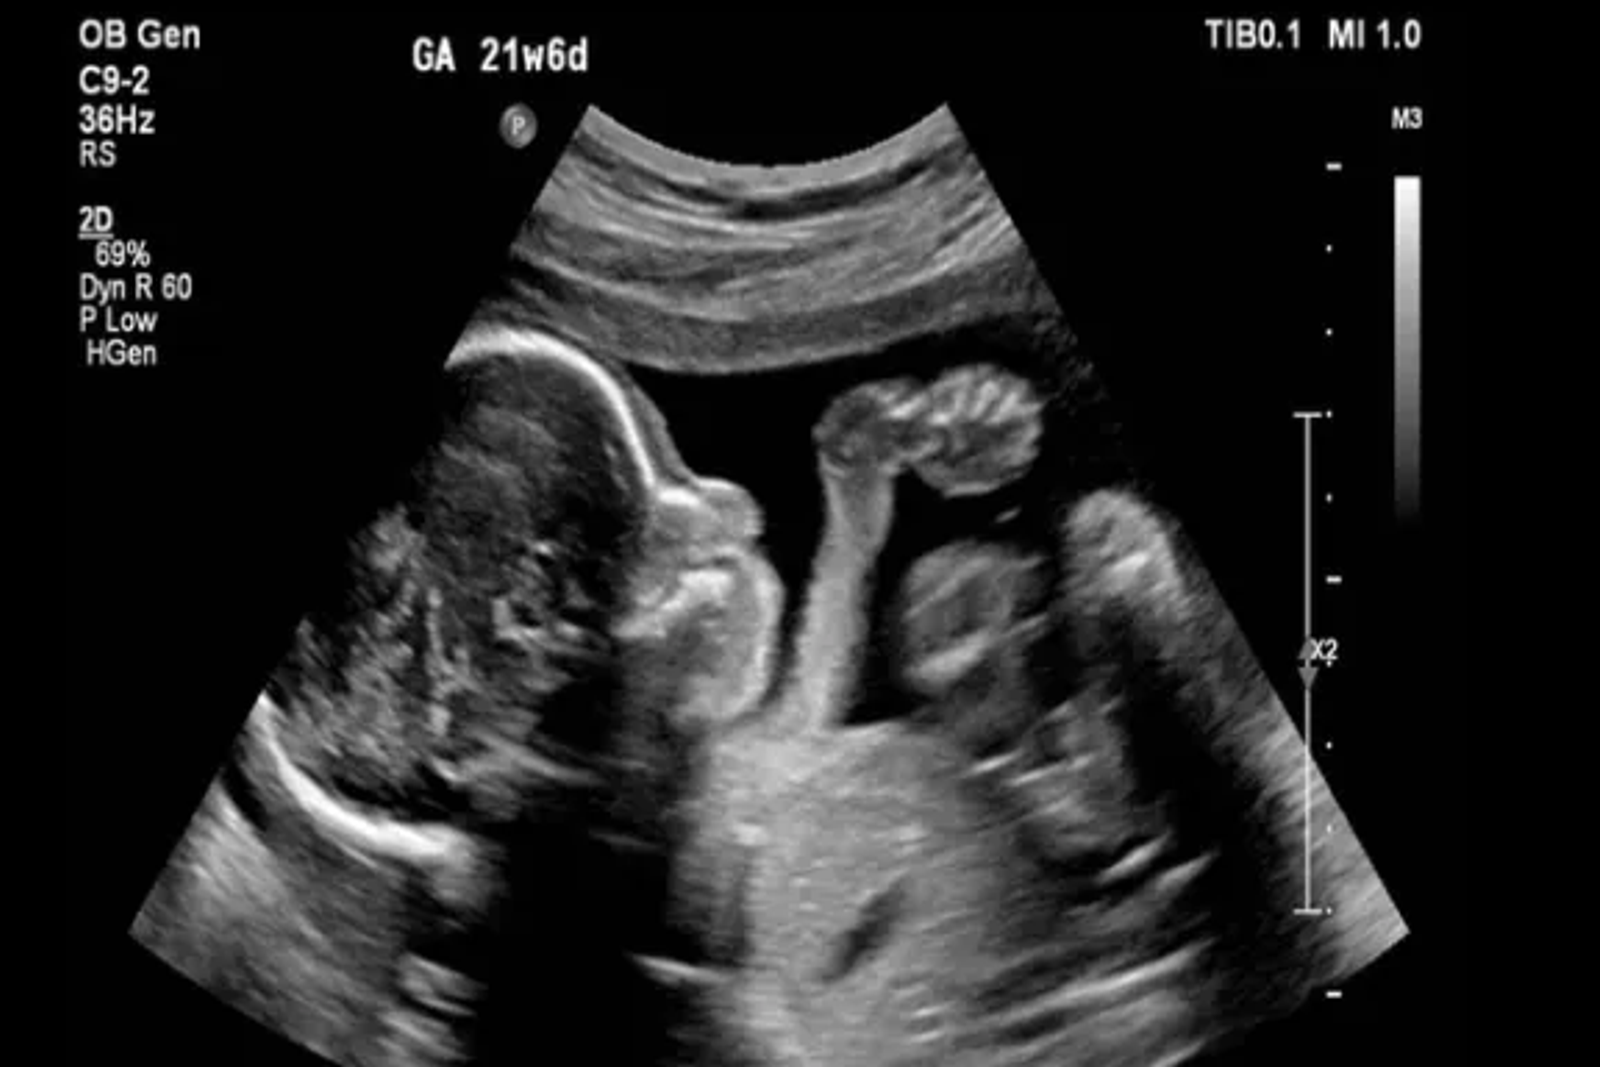

به گزارش دیلی میل، این یافتهها که در نشریه «مولکولار سایکایتری» منتشر شد، حاکی از آن است که هر گونه اختلال در روند زمانبندی شده و حساس رشد مغز جنین میتواند آسیبهای ماندگاری به ساختار مغز وارد کند؛ هرچند علائم آن ممکن است در بزرگسالی ظاهر شود.

پژوهشگران در این مطالعه، موشهای باردار را به سه گروه تقسیم کردند. گروه اول در دوران بارداری و گروه دوم در دوران شیردهی فلوکستین دریافت کردند و گروه سوم به عنوان گروه کنترل، دارویی دریافت نکردند.

نتایج جالب توجه بودند: نوزادان نری که در دوران جنینی در معرض دارو قرار گرفته بودند، دچار تغییرات زودرس در مراحل رشد مغزی شدند. این تغییرات در بزرگسالی به صورت مشکلات خلقی مانند ناتوانی در احساس لذت و شادی ظاهر شد.

در مقابل، نوزادان مادهای که از طریق شیر مادر در معرض دارو قرار گرفته بودند، تاخیر در مراحل حساس رشد مغزی را تجربه کردند و این موضوع در بزرگسالی به شکل مشکلات حافظه در آنها بروز کرد.